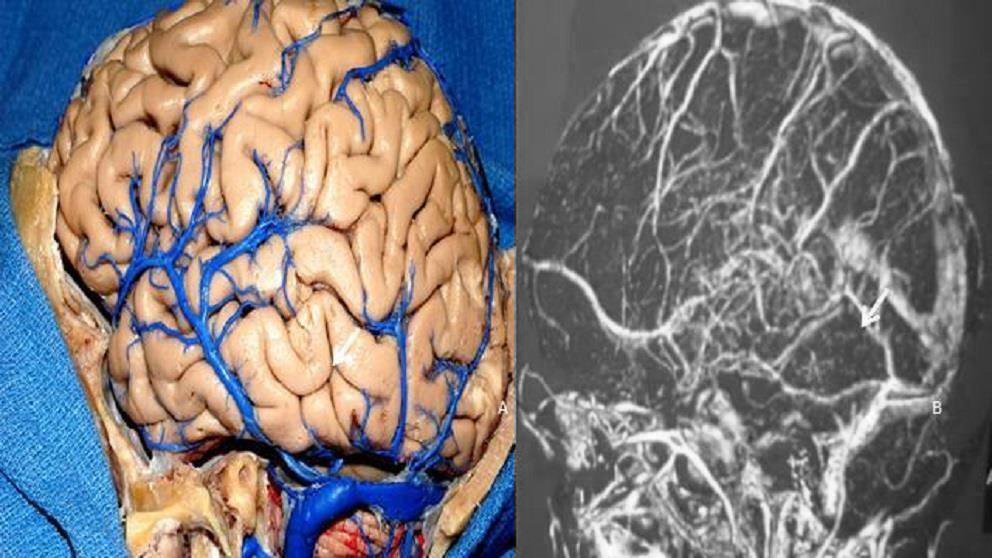

Se debe tener cuidado para preservar la vena de Labbé, que tiene una anatomía variable y generalmente ingresa al seno transverso 10 milímetros antes de su unión con el seno sigmoideo. La evaluación preoperatoria de la anatomía venosa con venografía por MRI es esencial para planificar este abordaje. La vena de labbé que drene al seno petroso superior o drene más de 2 cm anterior a la unión del seno sigmoideo con el seno transverso contraindica el abordaje petroso.

Figura 13: El estudio de la posición del drenaje de la vena anastomótica inferior (Labbé) se realiza para evaluar cuando se pretende realizar el abordaje petroso posterior. La vena de Labbé comúnmente drena en la unión de los senos transverso y sigmoideo (flecha). Pieza anatómica (A). Resonancia venosa (B).

Aunque se ha descrito una técnica en la que se abre el tentorio preservando la vena de Labbé(9), creemos que existe el riesgo de un infarto venoso cuando existe esta variación anatómica, principalmente si es una vena Labbé dominante o en un hemisferio dominante (afasia anómica debido a un infarto de la parte posterior del giro temporal inferior). En estos casos, optamos por un abordaje suboccipital retrosigmoideo. La incisión del tentorio continúa hasta la muesca donde se expone y preserva el nervio craneal IV (generalmente colocamos un hisopo de algodón para proteger el nervio en el fondo del campo quirúrgico mientras se corta la tienda del cerebelo). Algunas pequeñas venas del puente basal del lóbulo temporal anterior se coagulan y cortan, permitiendo una amplia exposición subtemporal. Aunque se pueden colocar cuidadosamente dos espátulas en el cerebro, apoyando el lóbulo temporal y el cerebelo, exponiendo toda la región petroclival de los nervios craneales III a VII y VIII, hemos observado en nuestros casos que no hay necesidad de usar espátulas. El nervio trigémino generalmente se puede ver desplazado posterior y superiormente. El tumor se desvasculariza por la coagulación bipolar de su inserción dural. Se debe tener especial cuidado al coagular el aspecto medial del tumor para evitar lesiones en el nervio abducens.